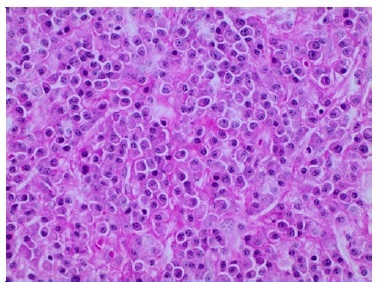

Além disso, não foi diagnosticada lesão mandibular no primeiro episódio. A paciente comunicou que omitiu o diagnóstico durante a anamnese por não acreditar ter relação com a odontalgia, e por ter feito exames laboratoriais e de imagem de corpo inteiro que descartaram qualquer sinal do mieloma, há cerca de trinta dias. Realizou-se punção aspirativa por agulha fina da área entumecida, não sendo observado presença de material líquido, sendo então optado pela realização de biopsia incisional (Figura 4), sob anestesia local, devido a necessidade de conclusão do diagnóstico. Durante o procedimento cirúrgico foi possível evidenciar um nódulo de superfície lisa, brilhante, avermelhada com estrias esbranquiçadas e friável a manipulação. A análise histopatológica (Figuras 5, 6 e 7), corada com Hematoxilina e Eosina, revelou proliferação de células de morfologia plasmocitóide, que apresentavam atipia, cromatina nuclear pontilhada e invasão do tecido conjuntivo, conferindo o laudo de mieloma múltiplo, sem necessidade de marcação imunohistoquímica, devido ao diagnóstico dessa lesão no passado.

Figura 5 Lencol de plasmocitos invadindo tecido conjuntivo fibroso (x100 - coloracao com Hematoxilina e Eosina)

Figura 6 Denso infiltrado de plasmocitos com núcleo grande e excentrico, nucleolo proeminente, moderado citoplasma e presenca de atipia (x200 - coloracao com Hematoxilina e Eosina)

Figura 7 Camada difusa e monotona de células plasmocitoides, apresentando cromatina nuclear pontilhada (x200 - coloracao com Hematoxilina e Eosina)